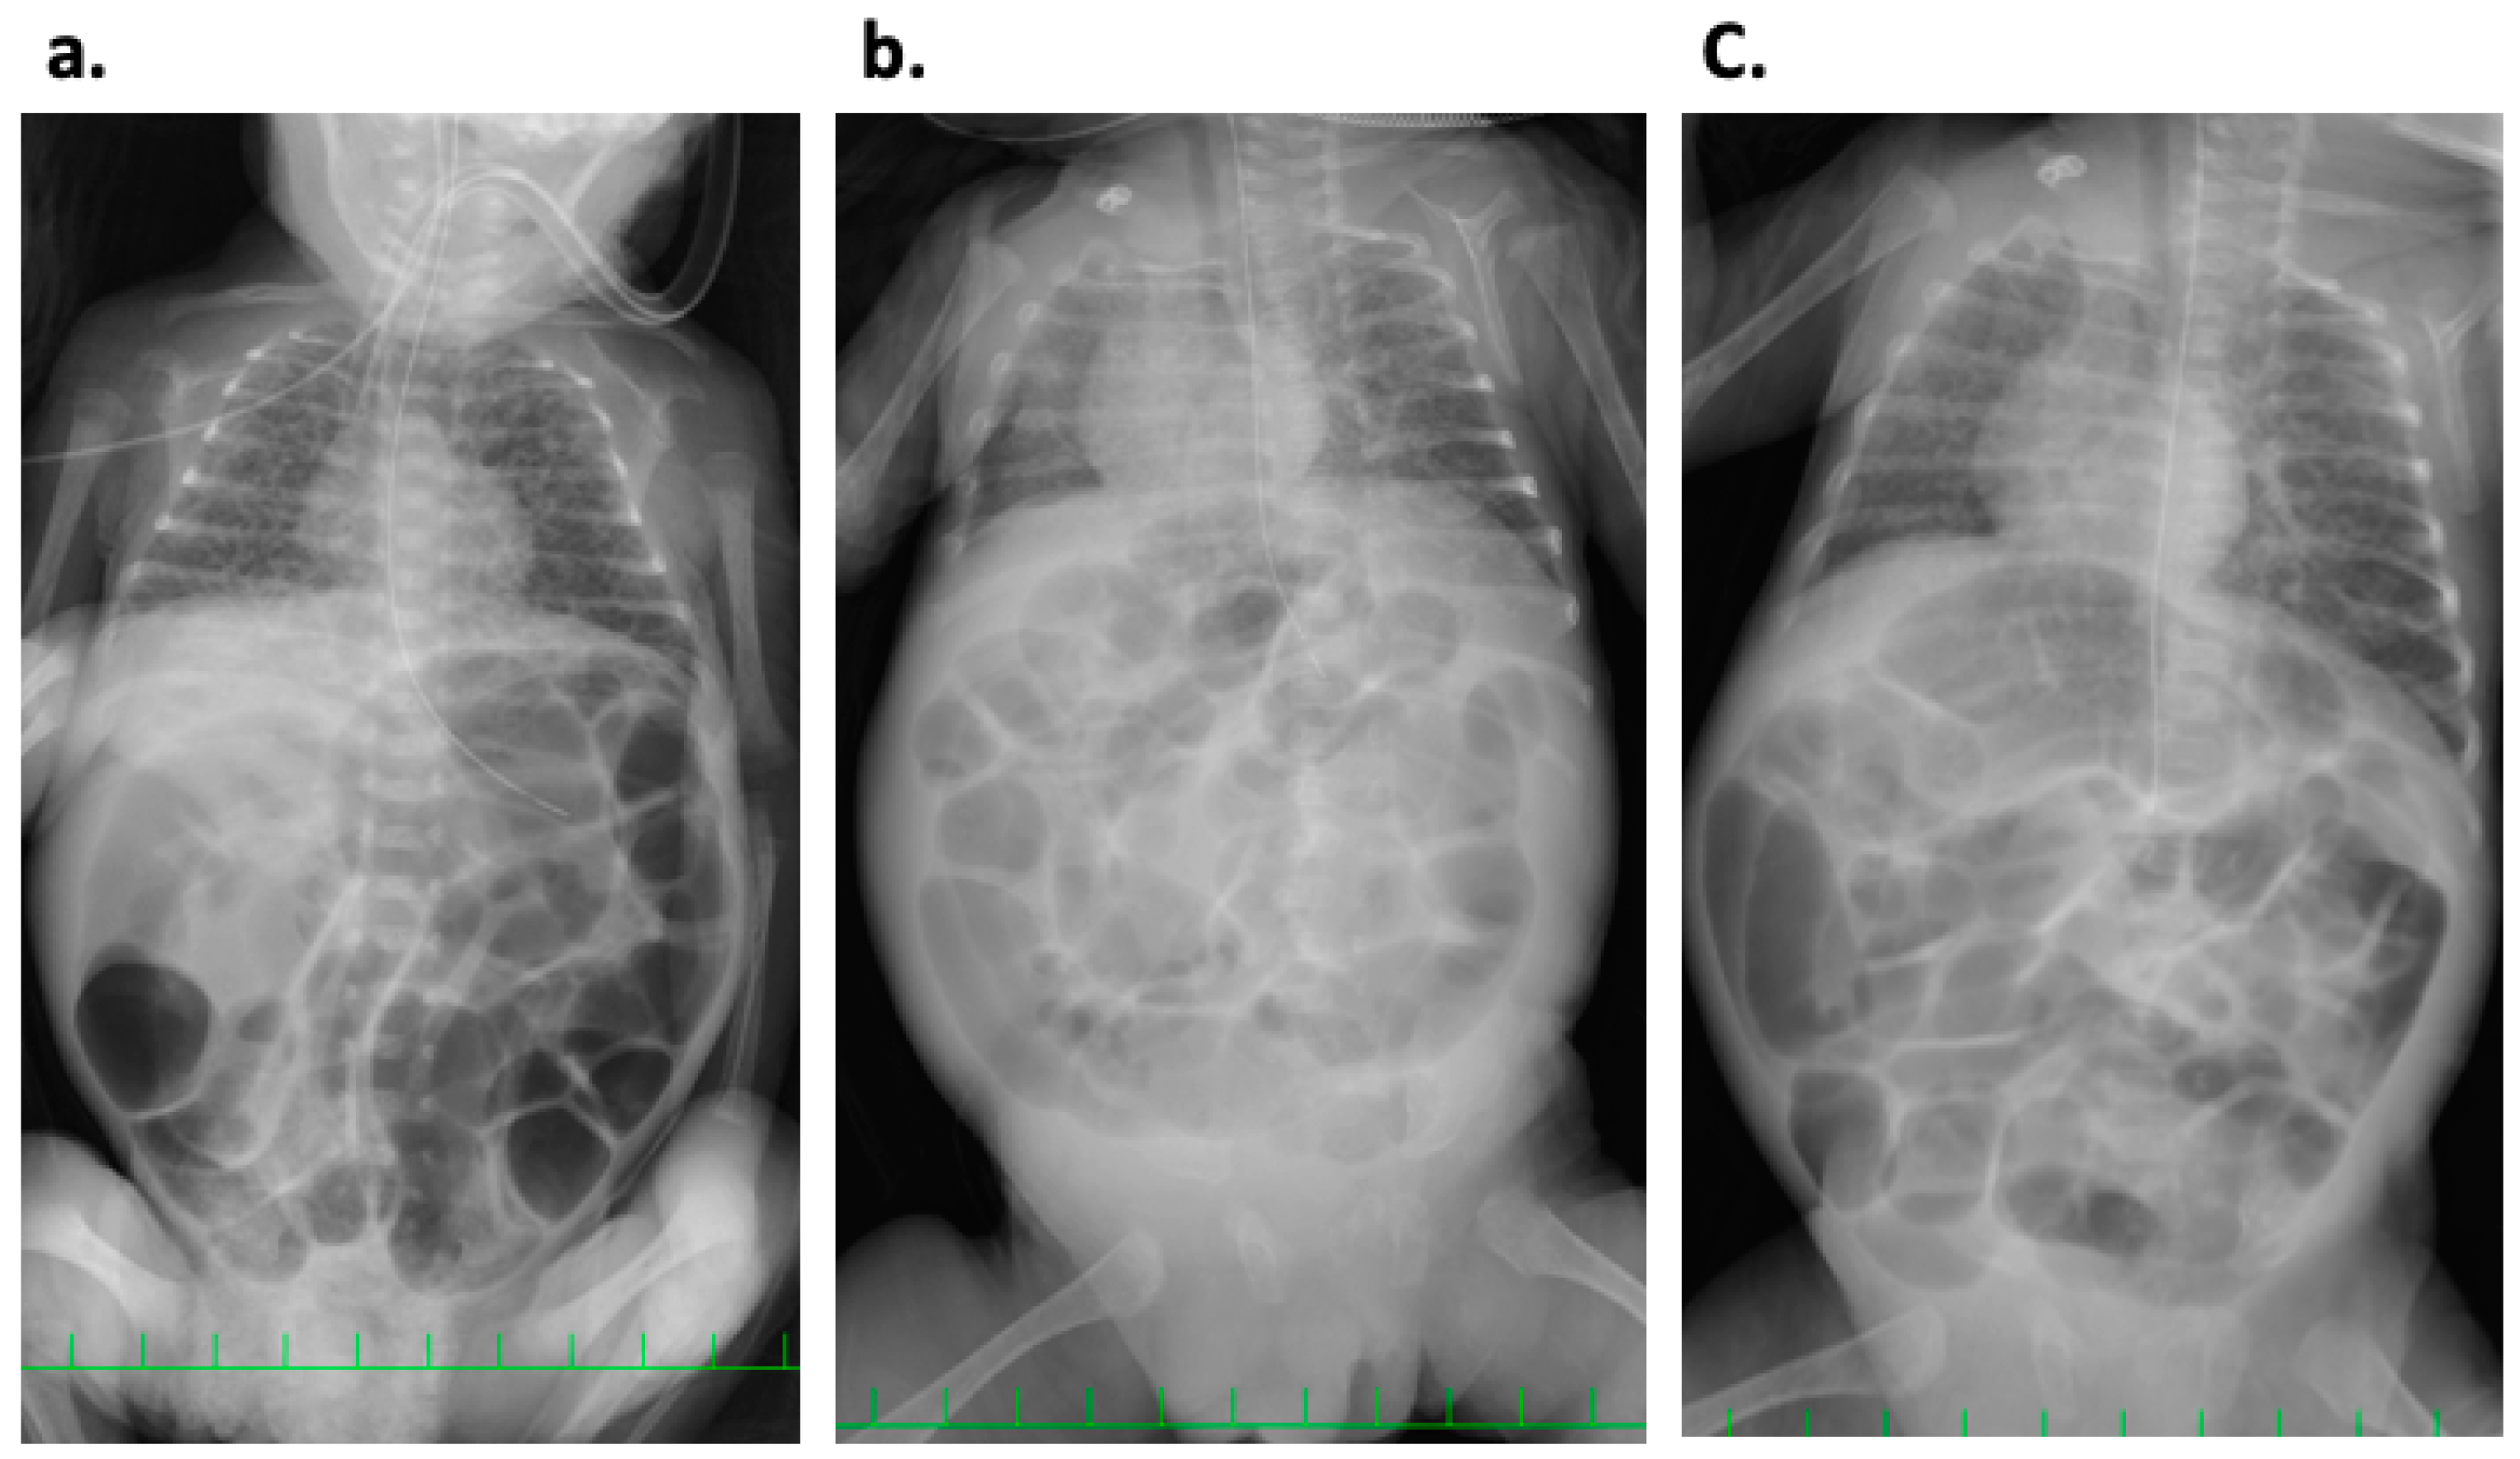

2. Case History